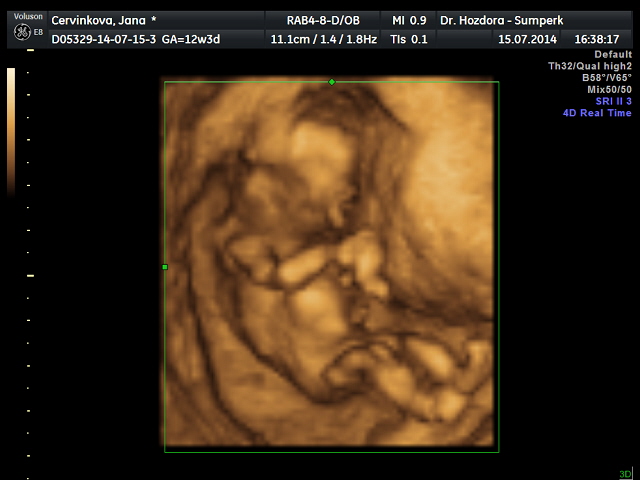

Děvčata srdečně zdravím...genetický ultrazvuk dopadl skvěle.....zítra se dozvím výsledky krevních testů a podle toho se rozhodnu,zda podstoupím nabízenou amniocentézu či ne. Pravděpodobně mám v bříšku holčičku,ale jistější to bude ve 20tt. dostala jsem flešku s obrázkama a kraťoučkým videem,za 3d fotečku jsem si připlatila. Doprovázel mě můj drahoušek a byl z toho docela paf. Mimčo bylo akční.....podle ultrazvuku mám velmi dobrý pocit a věřím,že výsledky budou v pořádku celkově. Jsem tak happy.